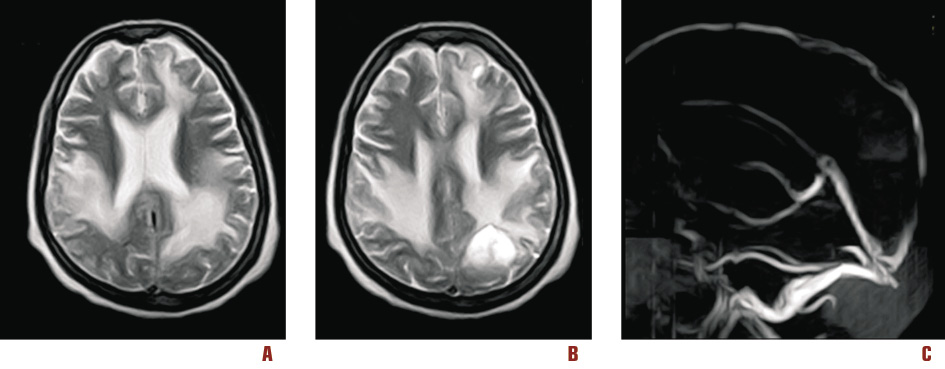

After two weeks of mechanical ventilation, a tracheostomy was performed. Atelectasis and ventilator-associated pneumonia were corrected with physiotherapy and antibiotics (imipenem 2 g/day and amikacin 1 g/day). A control MRI showed the recanalization of affected sinuses (Figure 2).

Figure 2. Follow up MRI and MRI venography that showed evolution of venous infarctions (A, B) and recanalization of superior and inferior sagittal sinuses (C )

After 31 days, the patient was discharged to rehabilitation unit. She appeared lucid, oriented and in a good consciousness state but she has a severe paresis of her left arm and leg. After two months of rehabilitation, neurocognitive functions have shown a strong recovery, even though her right hand still showed difficulty moving.